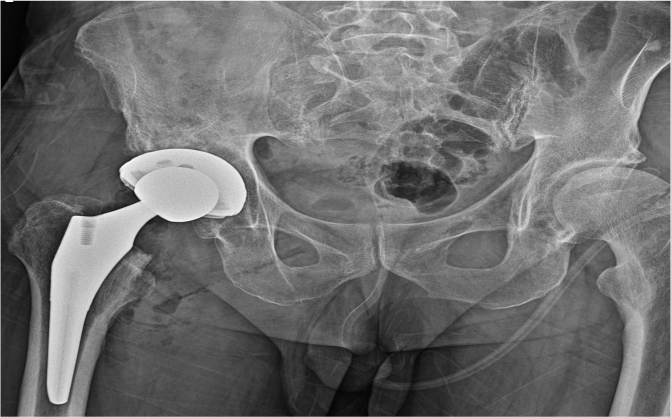

최고 수준의 진단과 치료, 비수술부터 인공 고관절까지

인공 고관절 치환술의 특징